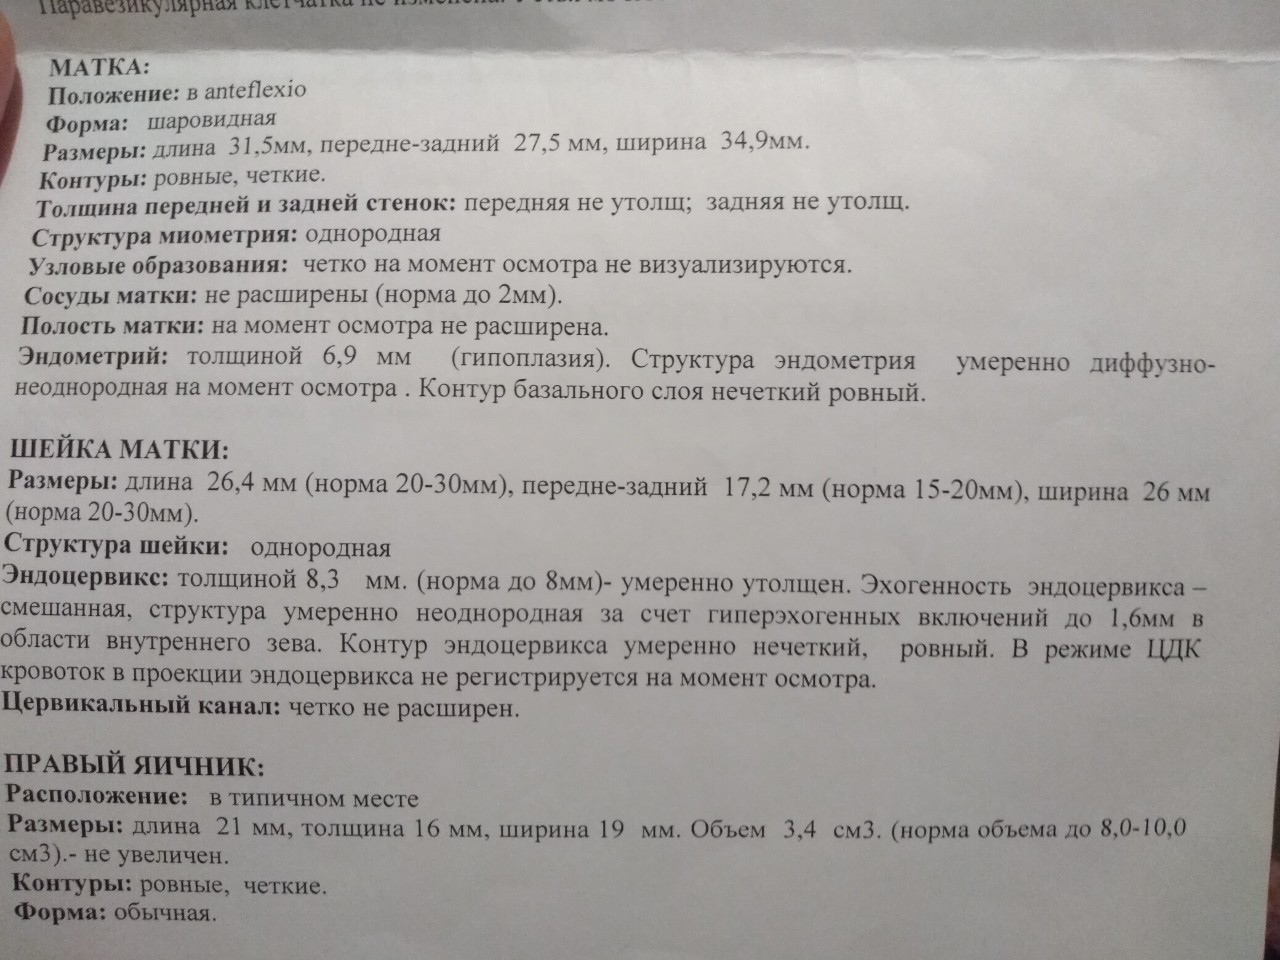

Медицинская диагностика: Гиперплазия эндометрия на УЗИ

Раздел: Мудрость в объективе